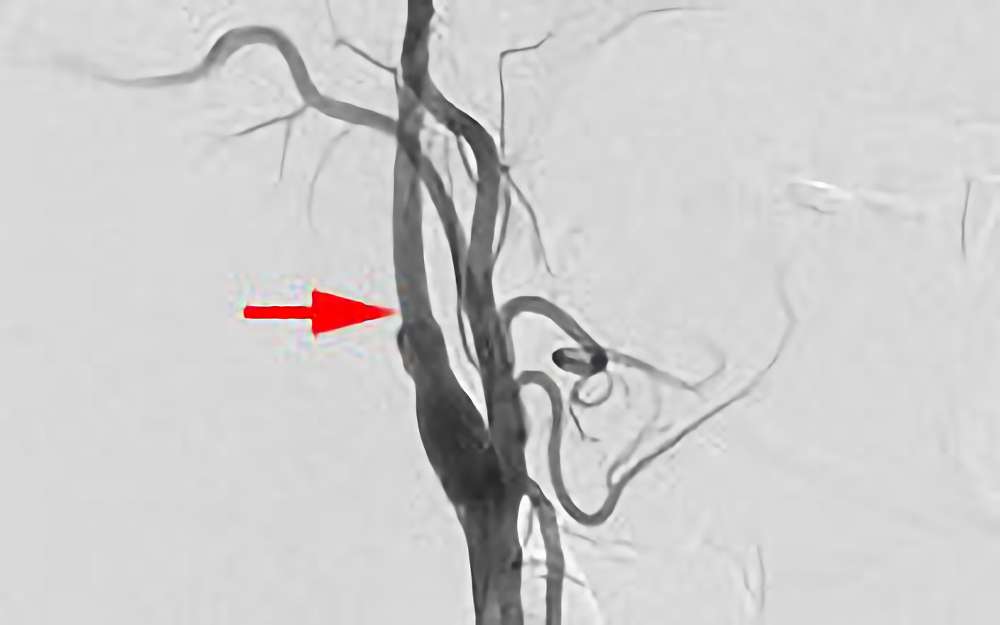

945

'20年11月11日

左頚部内頚 動脈狭窄症

30代

院内外来

'20年11月